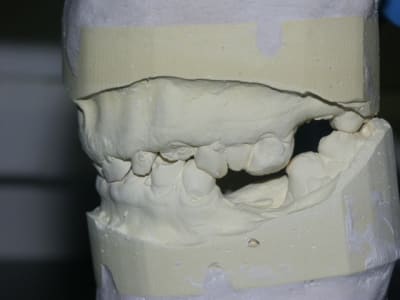

quelques rétroalvéolaires:

la 26 est morte: pas de mobilité mais lésion endo-paro distal irrécupérable. Si pose d'implant, faudra greffer le sinus avant.

En fait seule la 36 est très légèrement mobile.

suis pas syperchaud de garder 31 et 41 mais l'anatomie radiculaire de la 42 n'est pas hyper favorable à la réalisation d'un bridge avec des IC.

je pense qu'il faudra mieux sacrifier la 22 avec sa lésion.

vraiment, je cale un max sur la globalité de ce cas par la combinaison bruxisme-égression-occlusion-taille défavorable des racines.

la radio des dents 12-13 illustre parfaitement mes doutes:

Après avoir vu en conf Genon procéder à des chir paro (gingivectomie à biseau ext + plastie osseuse) sur les secteurs antérieurs, chez des bruxos pour gagner de la surface dentaire (en vue de faire les CCM par la suite) sans augmenter de façon inconsidérée la DV, je me disais que j'aurai pu proposer la même solution chez ce patient.

Oui mais..., c'était avant de faire la radio où on voit de petites racines et bien coniques par dessus tout... bref tout ce qui peut être défavorable et contre-indiqué cette solution... :-(

En haut tu ne gardes que 13 à 21 pour faire une barre.

Il faut mettre en articulateur et étudier la position relative des maxillaires si l'on augmente la DV. En général, c'est beaucoup plus facile à gérer avec de l'amovible que de la fixe à cause des décalages entre les dents maxillaires et mandibulaire. Il est vrai que là, ce ne sont pas seulement les dents qui ont égressé, mais bien l'os alvéolaire autour.

PAC ou PAP je veux bien mais a mon avis sans une Correction du volume osseux excedentaire anterieur (qu'il vienne du maxillaire ou de la mandibule).

bé oui. voir les procés alvéolaires mxillaires. Je pensais faire une chir paro, tailler dans la viande et dans l'os pour réduire cette compensation mais après j'aurai plus beaucoup d'os autour des dents (qui ont de petites racines)... donc????